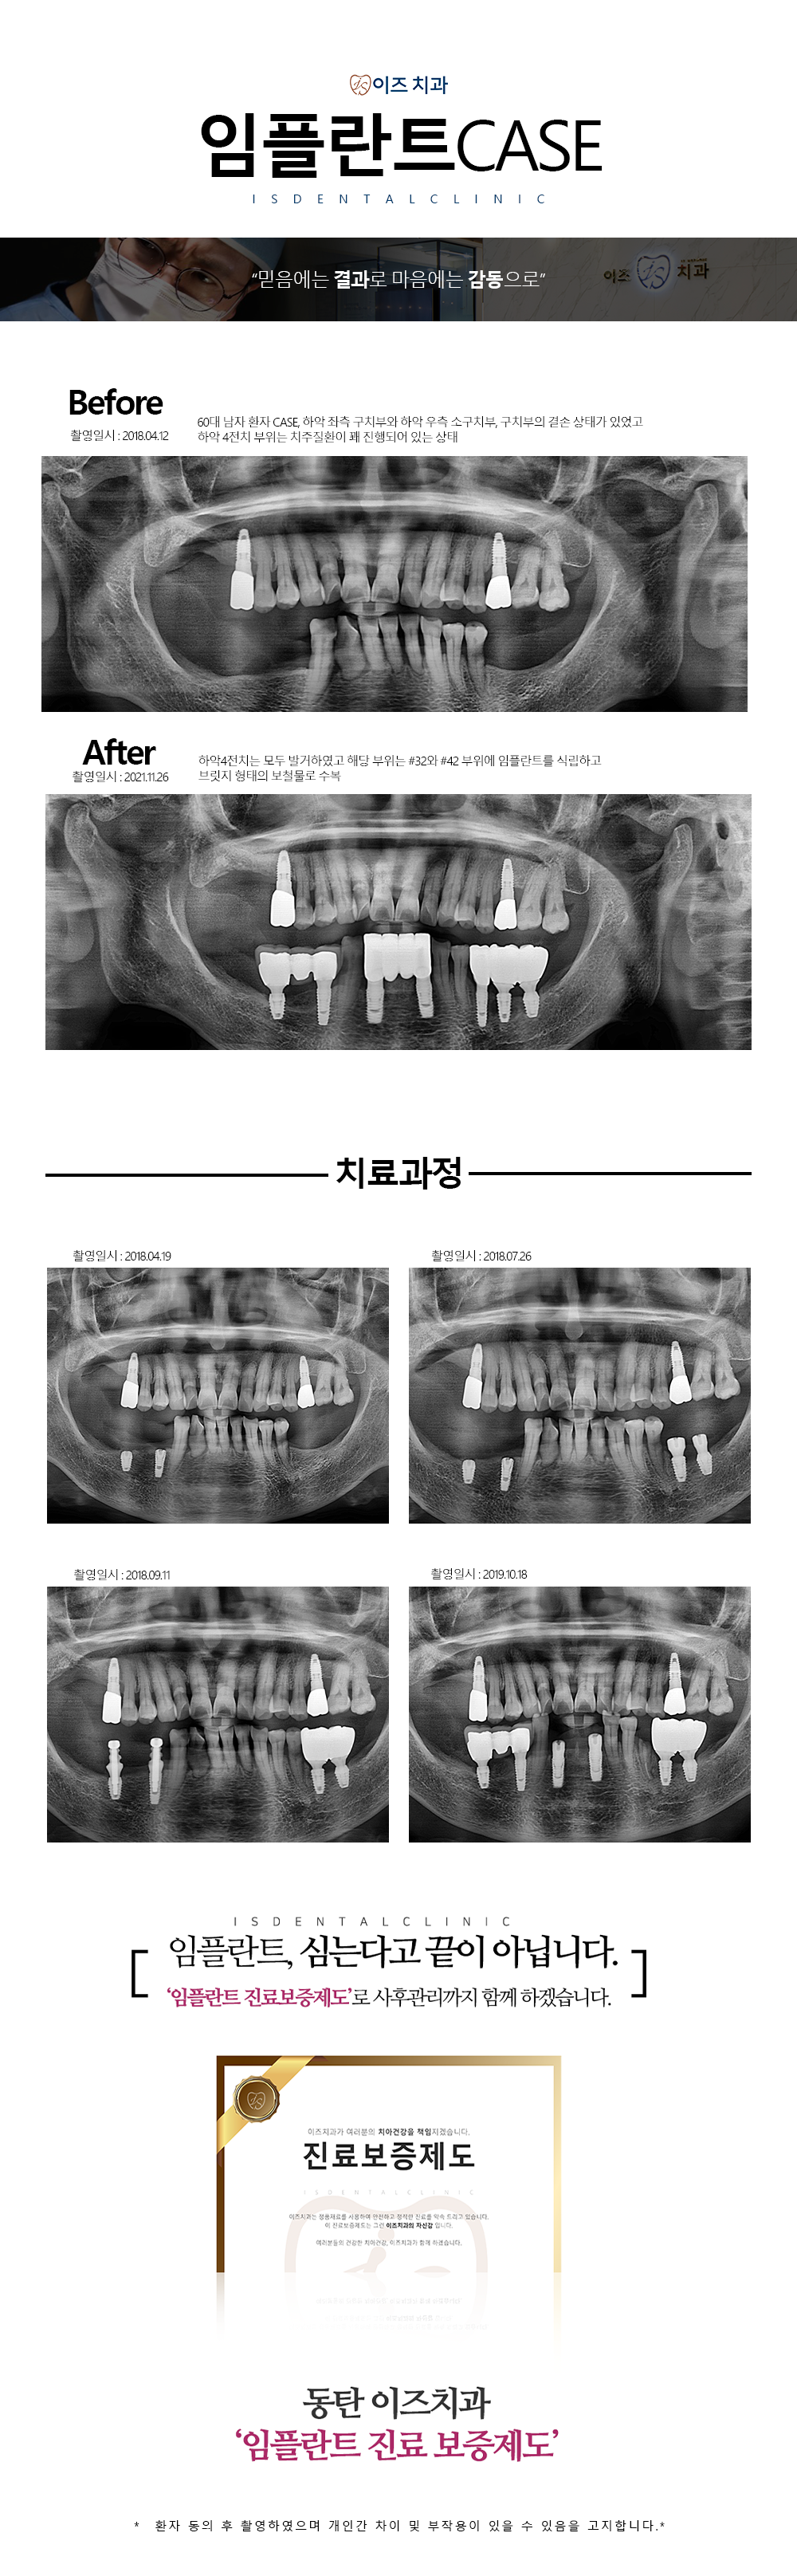

오류안내 페이지 | 치료 끝이 좋은 치과, 이즈치과